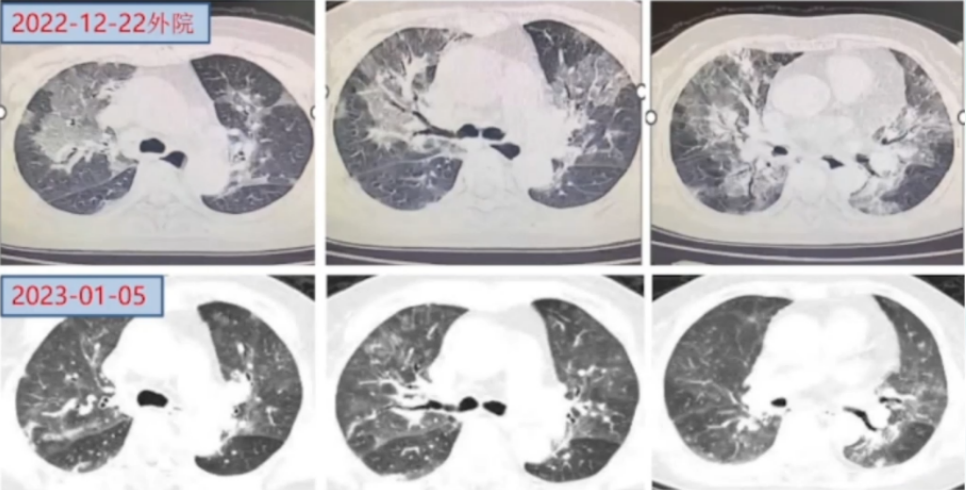

9. 后续治疗方案

醋酸泼尼松片25 mg/d×3周→20 mg/d×6周→吗替麦考酚酯0.5 g bid→醋酸泼尼松片15 mg/d;吗替麦考酚酯0.5 g bid。

2023年4月4日复查胸部CT:两肺渗出大部分吸收(图7)

图片

7  患者胸部CT变化